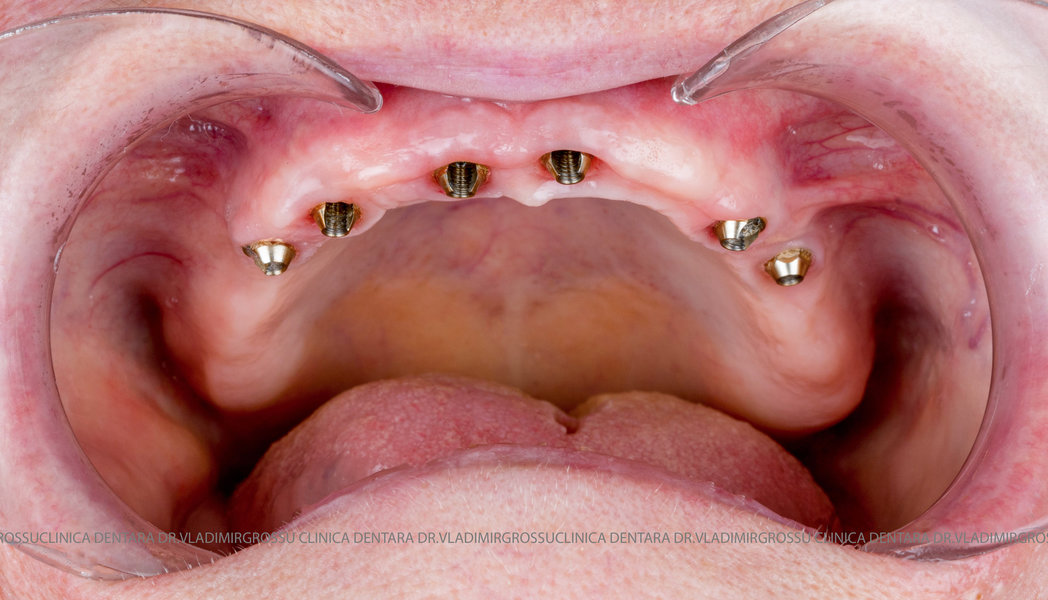

Cazuri clinice conceptul All-on-6

Caz 1